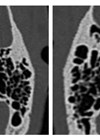

SCOTLAND preoperative tympanomastoid CT temporal bone mnemonic system

Learning how to interpret a CT scan of the temporal bones can be a daunting task, especially for a head and neck surgeon like me! However, to make life easier, the authors have devised a useful system to help cover...